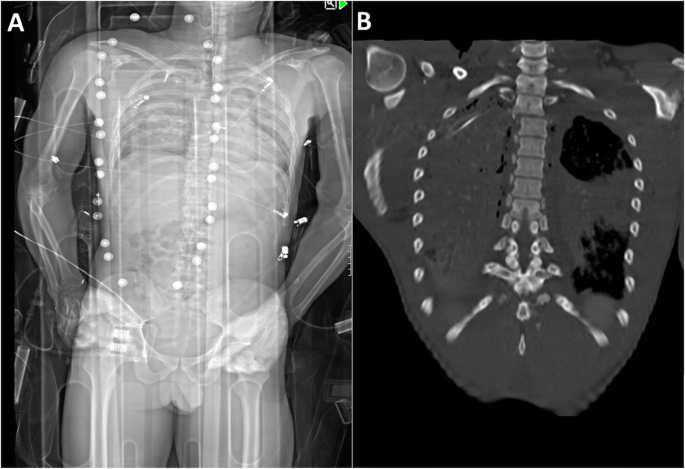

Examples of a misdiagnosed and correctly identified injury are shown in Figs. 3 and 4.

Example of a missed unstable injury using anterior-posterior Lodox Statscan (AP-LS). An unstable spinal injury fo the second and third thoracic vertebra shown in AP-LS (a), and the full-body CT scan (b) of 46-year-old men after falling from a height. None of the three observers identified the injury in AP-LS